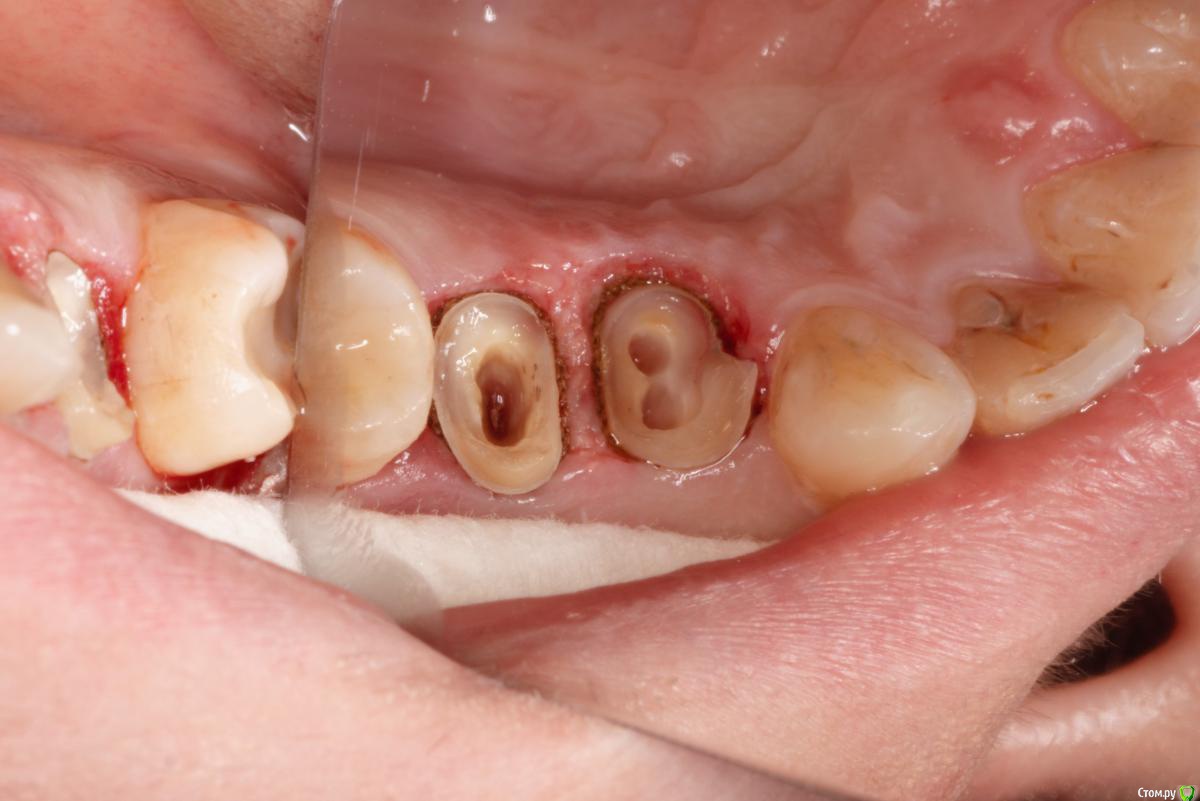

skeettrap Опубликовано 5 июля, 2016 Поделиться Опубликовано 5 июля, 2016 Стандартная ситуация : коллега попросила сделать родственнице (мужа) за неделю - во время краткосрочного визита из Израиля.Исходная ситуация 14,15 сильно разрушены с временными пломбами и наплывшей десной(фото не сделал).На первом этапе сделаны культевые вкладки прямым методом (десну подрезал бором). Постановка вкладок на следующий день, изготовление временных коронок, снятие слепков. Через 2 дня - фиксация. Ссылка на комментарий

Bratok Опубликовано 6 июля, 2016 Поделиться Опубликовано 6 июля, 2016 Бедный феррул )) хир удлинение не стали делать? Ссылка на комментарий